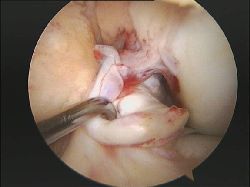

2 pensamientos sobre “rotura_LCA_B”